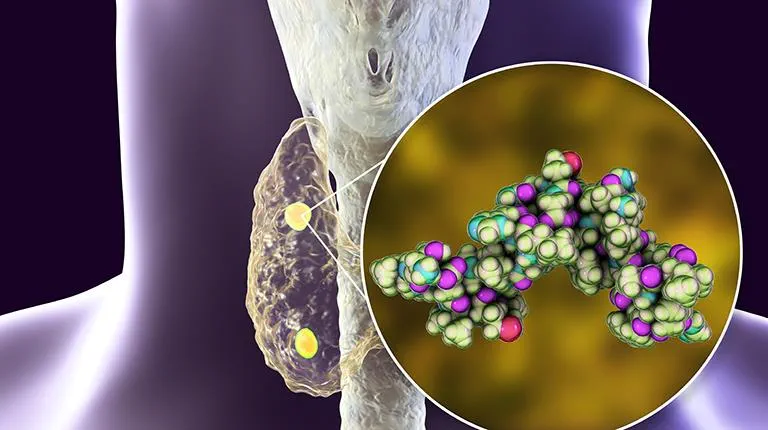

Ondansetrona e o risco de morte súbita em hemodiálise

Ondansetrona e o risco de morte súbita em hemodiálise

Como assim risco de morte súbita com Ondansetrona? Atenção especial aos pacientes com polifarmácia e risco de QT longo!